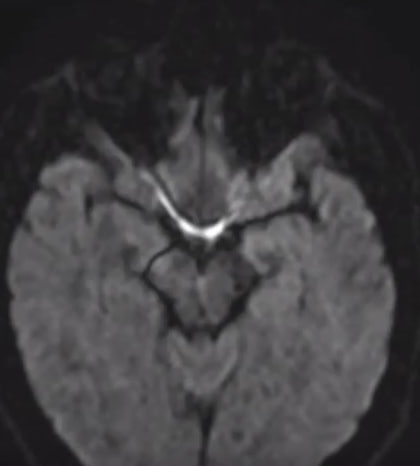

Советую не турничок, но гравитрон, мудила))

>>1628567

Посетил второй раз центр рассеянного склероза с результатами МРТ. Диагноз подтвердился, хотя внутри я все еще надеюсь, что это не ОНО.

Легкая головная боль прошла за это время, но упадок сил и сонливость никуда не делись.

Не могу понять, ухудшается ли у меня координация движений или стагнирует, но мне кажется, что я стал меньше пользоваться правой рукой.

Днем одолевает жуткая сонливость, не покидает ощущение воспаленности внутри, как на начальных стадиях ОРВИ, при этом у меня нет повышенной температуры, сложно сфокусироваться на одной задаче на работе, еще сложнее переключаться между задачами или думать и говорить.

Хотя я сплю в рабочие дни по 5 - 6 часов, но предыдущие три года жизни в таком ритме не вызывали у меня таких больших проблем.

Хотел бы я как-то если не восстановиться, то хотя бы убрать усталость, сонливость и ощущение воспаленности...

Есть тут еще анонимы с РС? Как поддерживаете себя?

Я еще позапрошлой зимой думал о том, что регулярный сон в 5 - 6 часов на фоне хронической депрессии ни к чему хорошему не приведет, а теперь диагноз заставил еще больше заняться самокопанием и ощущением того, что я многое не успел в жизни.